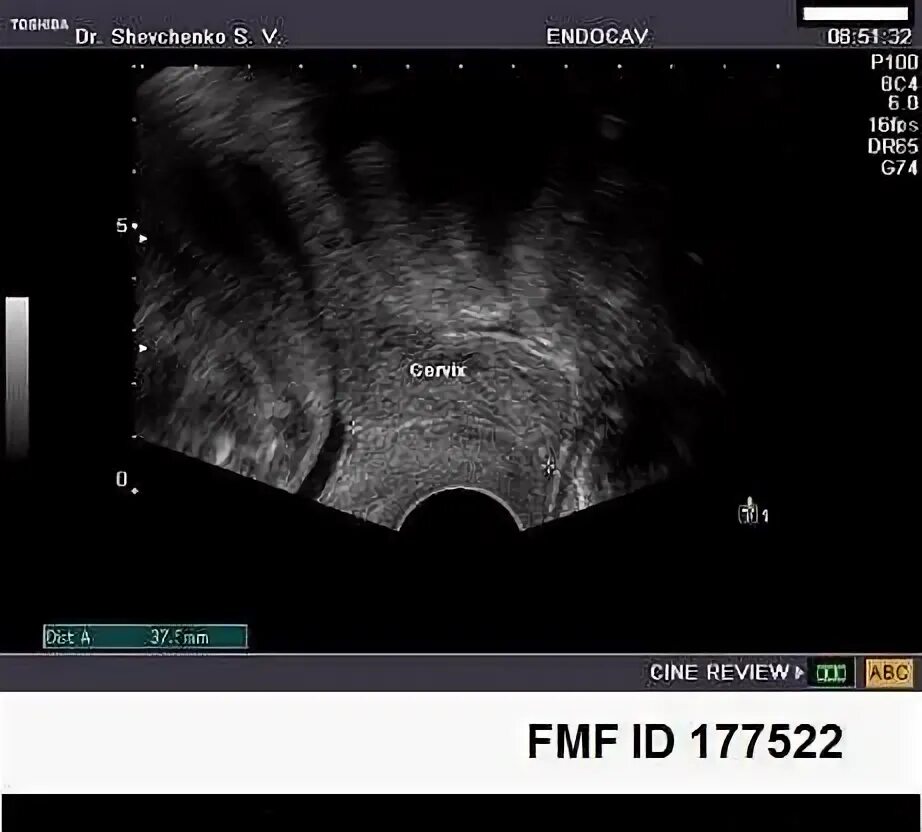

Цервикометрия при беременности как делают